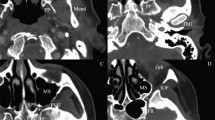

The transverse-sigmoid sinus (21 cases, 70.0%) was the most common site of dAVF triggering PT, followed by the hypoglossal canal (3, 10.0%) and the middle cranial fossa (2, 6.7%; Fig. 3, Table 2). The venous drainage directly into the dural venous sinus or meningeal vein (Borden type I; 22 cases, 73.3%) pattern was more common than sinus drainage with cortical venous reflux (Borden type II; 8 cases, 26.7%; Table 3). Among the eight dAVFs with a Borden type II venous drainage pattern, seven were located at the transverse-sigmoid sinus and one at the confluence of sinuses (torcula). No patient in our series showed venous drainage directly into subarachnoid veins with cortical venous reflux only (Borden type III) on TFCA.

Representative brain MRI images and TFCA findings of (A) transverse-sigmoid sinus dAVF, (B) hypoglossal canal dAVF, and (C) middle cranial fossa dAVF. (A) Left external carotid artery angiogram in anteroposterior and lateral views shows a dAVF with feeders from left middle meningeal artery (yellow arrows) and left occipital artery (red arrow), draining into left sigmoid sinus (white arrows). (B) Left external carotid artery angiogram in anteroposterior and lateral views shows a dAVF with feeders from left ascending pharyngeal artery (yellow arrows), draining into left internal jugular vein (white arrows at venous sac). (C) Unsubtracted and subtracted left external carotid artery angiograms in lateral view show a dAVF in left middle cranial fossa with feeders from left middle meningeal artery (yellow arrows), draining into left inferior petrosal sinus (white arrows at venous sac).